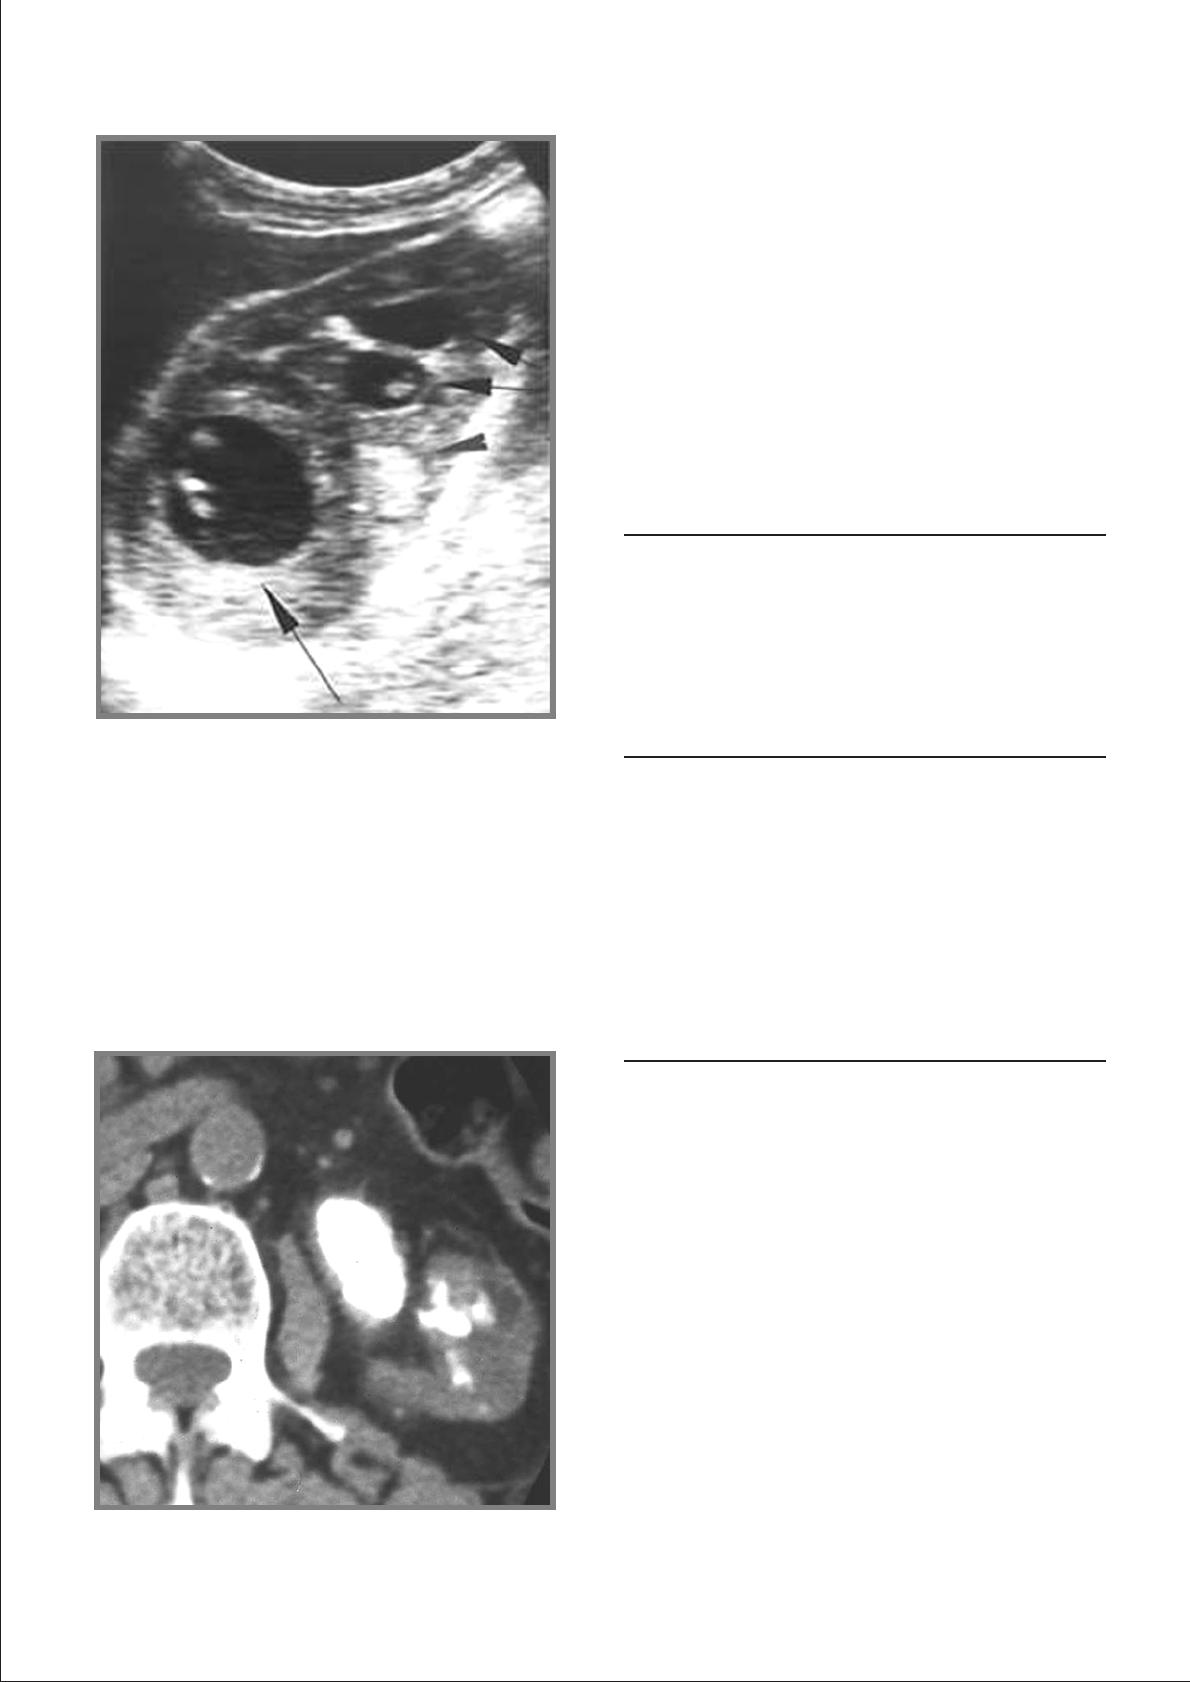

Echographie

L'échographie [1, 2] est moins performante que l'UIV ou

la tomodensitométrie. Elle est systématique en cas

d'altération de la fonction rénale. Elle permet de rechercher

des lésions rénales et des cavités exclues qui échappent

à l'UIV, de préciser l'origine d'un rein muet et de guider

les ponctions aspirations des cavités mais également les